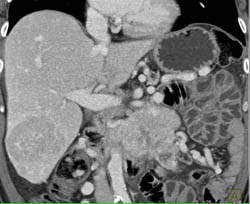

Pancreatic Carcinoma